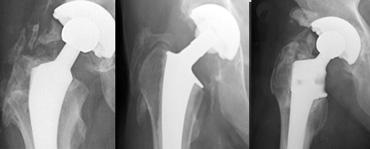

The case on the left is for several reasons not ideal :

– Vị trí cup quá cao và quá nghiêng về phía ngoài.

– Độ nghiêng sang bên quá nhiều.

– Lượng xi măng chèn lấp quá nhiều.

– Các vít được đặt quá nằm ngang (ứng suất quá lớn).

– Vùng thấu quang ở vùng II và III > 2 mm.

Đặc biệt, vùng thấu quang ở các khu vực này rất gợi ý đến tình trạng lỏng khớp.

Trong quá trình theo dõi, sự di chuyển lên trên kèm theo độ nghiêng tăng dần được ghi nhận, gây ra gãy vít cố định.